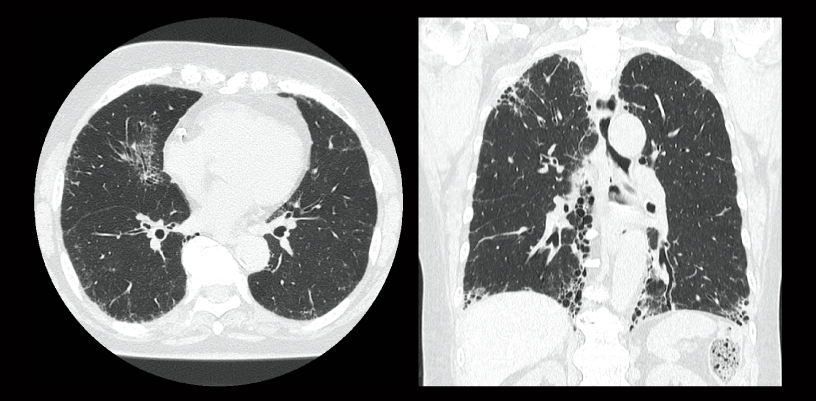

Interstitial pneumonia

Lung screening (CTDlvol: 2.0 mGy)